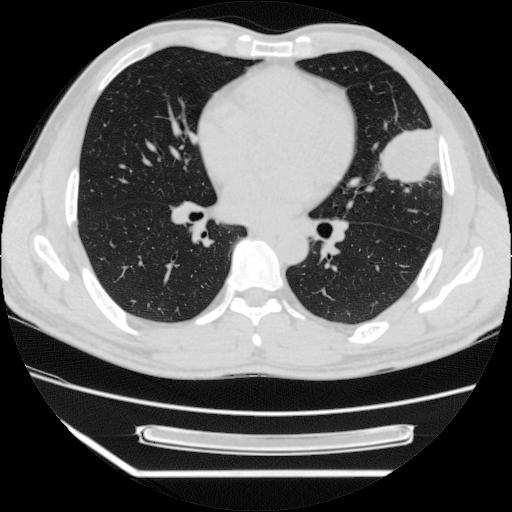

病灶发生在下叶,密度均匀,边缘模糊、毛糙,周围血管纹理增强扭曲改变,靠近胸膜处病灶胸膜反应明显。

支持考虑---球形肺炎。

左肺舌叶病变。主体病灶呈类圆形中心密度低,成液化趋势周边班片影分布

考虑肺脓肿